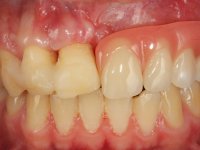

Paciente do sexo masculino, com 22 anos de idade e não fumador. Apresentou-se na consulta 6 meses após um acidente de viação em que perdeu os dentes 21, 22, 23 e 24. Os dentes 12 e 11 apresentavam mobilidade grau 3 apresentando-se também com extracção indicada. A arquitectura gengival da zona desdentada apresentava-se retraída e planificada.